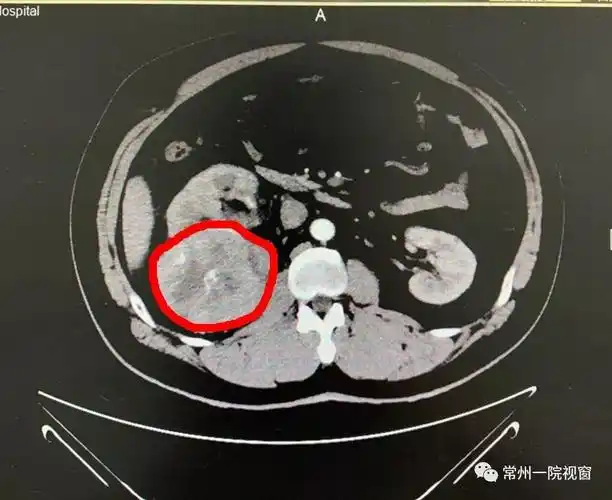

"右侧肾脏有一个直径约10cm的血肿,可能是肿瘤而且已经局部破裂,导致